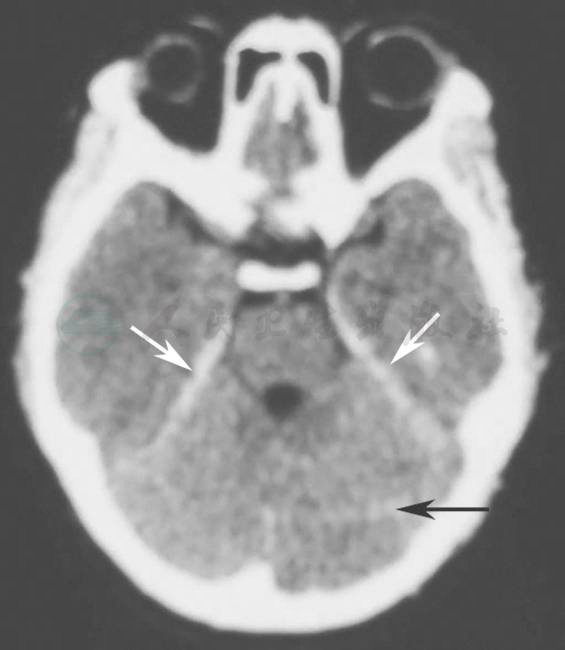

患者3个月前无明显诱因出现头晕、头痛、恶心、喷射样呕吐、耳鸣、视物模糊和双下肢多发散在出血点,当地医院查血小板减少,最低降至19×109/L,头颅CT示蛛网膜下腔出血(图1),诊断为“特发性血小板减少、蛛网膜下腔出血,眼底出血”,予静脉用丙种球蛋白、激素冲击、止血、补充血小板、脱水降颅压及营养神经等对症治疗,患者头晕、头痛症状有所缓解,仍视物不清,右眼视力为0.05,左眼仅视手指移动。

图1 头颅CT示蛛网膜下腔出血

黑色箭头指示左侧小脑半球,白色箭头指示双侧小脑幕,均为高密度影,考虑存在蛛网膜下腔出血